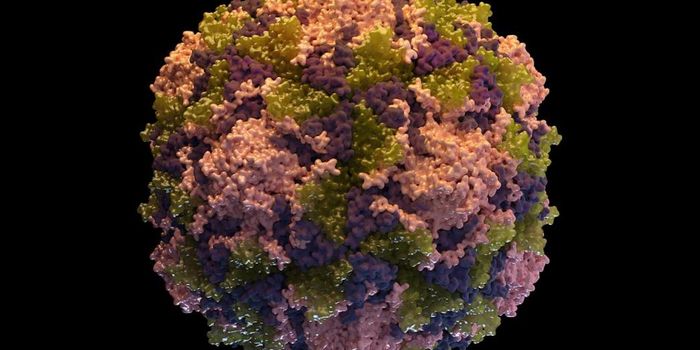

AUG 07, 2022MicrobiologyPolio is a disease caused by the poliovirus. Polio can cause flu-like symptoms like nausea, headache, fever, and sore th ...